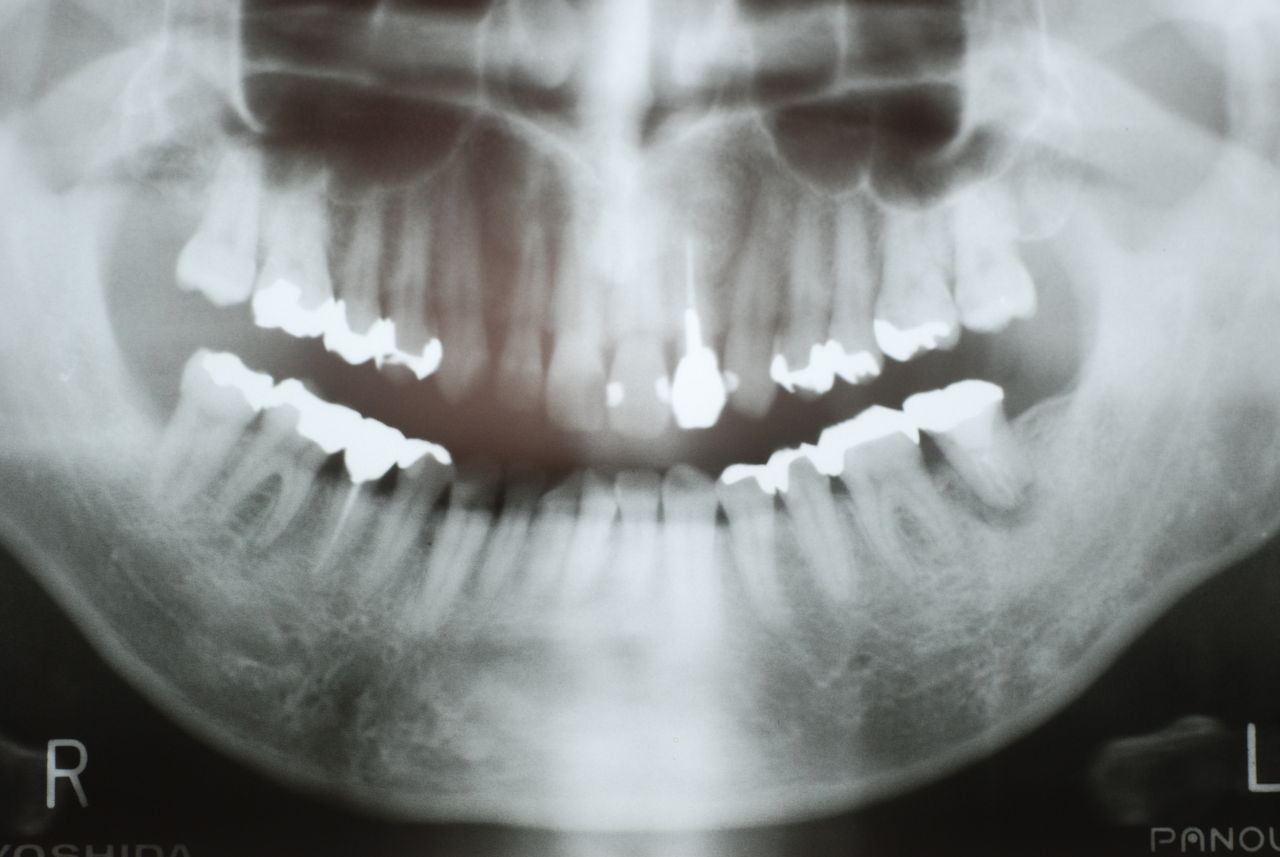

なかなかブラシの使い方ができていないようで、歯磨きと歯周病でのブラシの使い方は別なのですが、習ったことも検査もされずに金属を被せたりしているようで、これからも歯医者さんで抜かれたり、その後にインプラントのような高価な“クギ”を打ち込まれる方が増えるかと思うと残念です。

被せても、詰めても病気は治らないのですから。又病気の元になり易い不適合な差し歯や金属、インプラントがあればそこからバイキンが侵入して体に悪さもしやすいのではないかと心配しています。

歯周病と根尖病巣(根管内とは違う)の菌は同じだとか、所謂biofilm感染症なのだと。